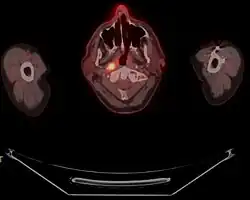

![]() | |

| Micrograph showing a nasopharyngeal carcinoma positive for Epstein-Barr virus-encoded small RNAs (EBER). | |